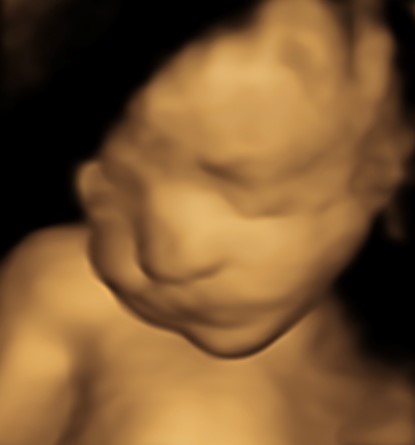

Monmouth County’s First 4D/5D/HD Live Ultrasound Studio

4D/5D/HD Ultrasound Gallery

Gallery